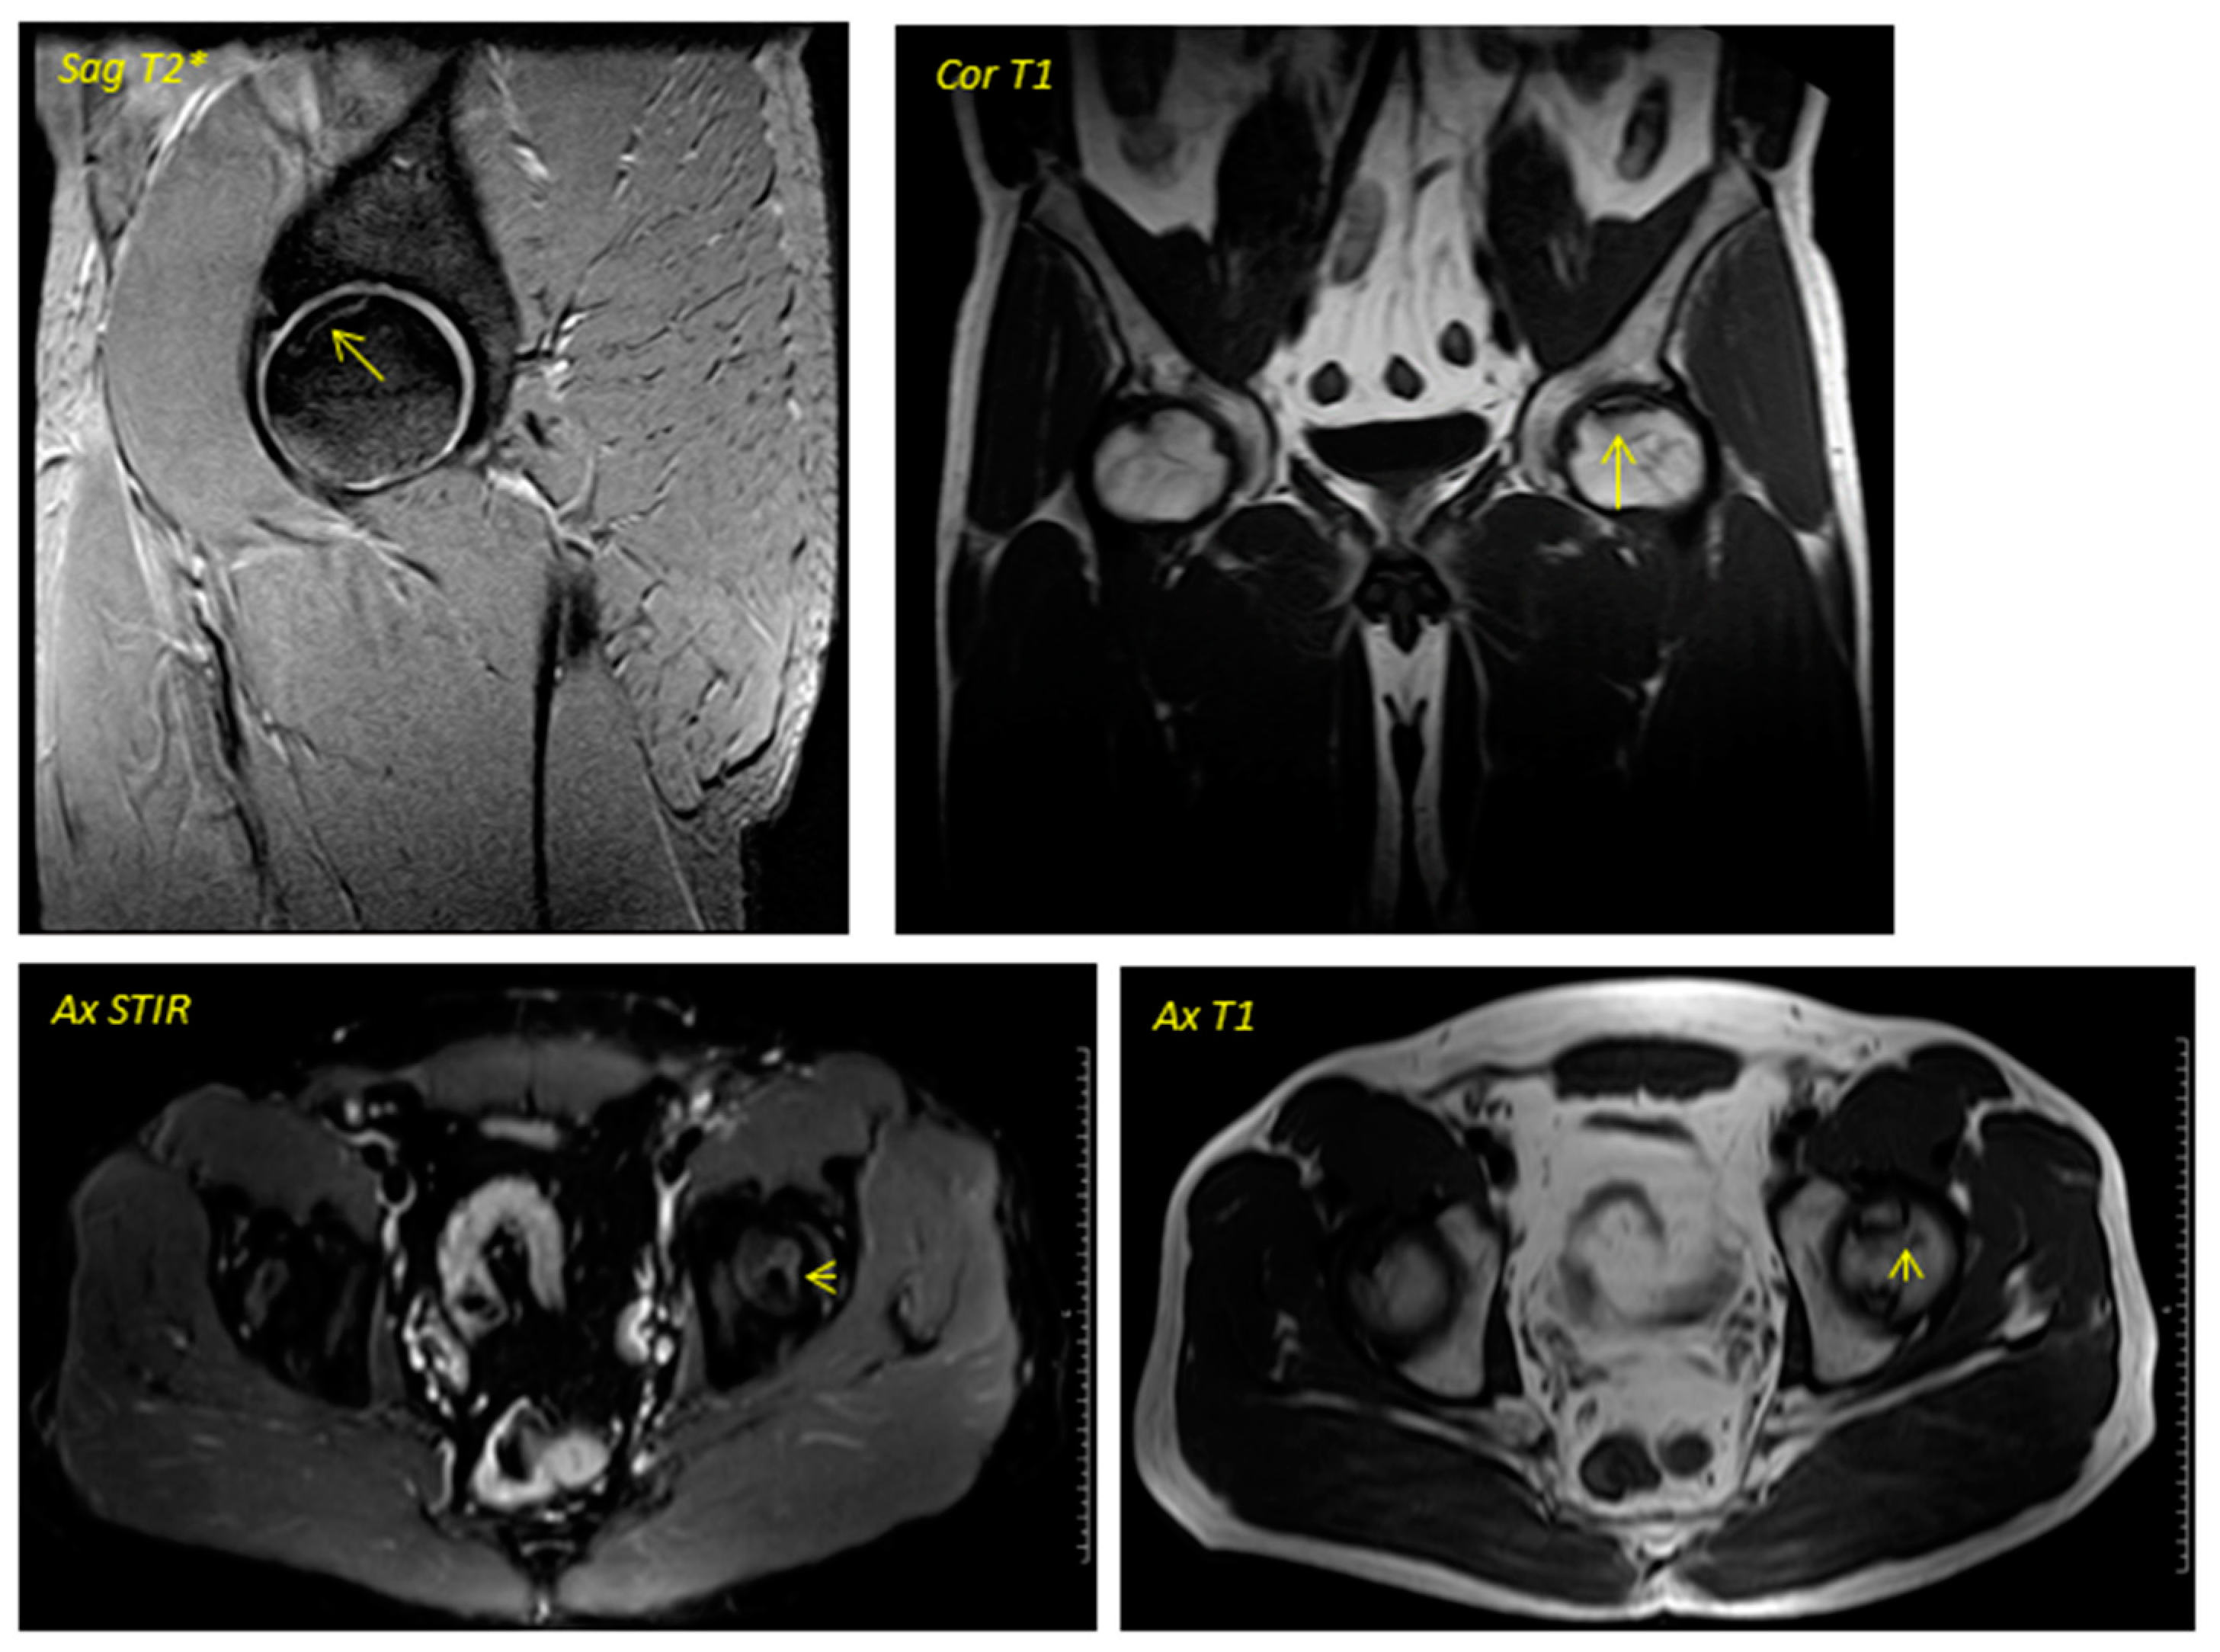

Figure 2. Post-surgical Magnetic Resonance Imaging corresponding to the patient in Figure 1 was performed in April 2016. Ax T1 (axial T1 plus contrast plus fat suppression–(A) Axial plus caudal incidence and axial (B) plus cranial incidence). Trocar entry is visualized in all images.

Regarding the imaging studies, several findings were observed in the radiographic evolution during the 12-month follow-up (Figure 1 and Figure 2). First, changes in the direction appeared in all cases from the sixth month, not being evident in earlier stages. Second, radiographic stabilization was achieved in 62.5% of the patients (n = 5) during the first year after surgery. Third, two patients (25%) showed the progression of the necrotic zone, while in one (12.5%), signs of re-ossification were evident. Despite observing descriptive differences, the p-value was not statistically significant for the latter parameter (p = 0.317).

Regarding the dynamics in the MR images, two patients were baseline in stage IA of the ARCO classification (25%), two in IIA (25%), and four in IIB (50%). In the same way, a stabilization in the staging of the post-surgery images was observed in seven of the eight patients studied (87.5%), with only one case (12.5%) evolving from grade IIB to grade IIIA, presenting subchondral collapse of the femoral head, which was already evident from the sixth month onwards. Descriptively, changes were observed, but they were not statistically significant. No significant variability was observed in the imaging findings between patients.